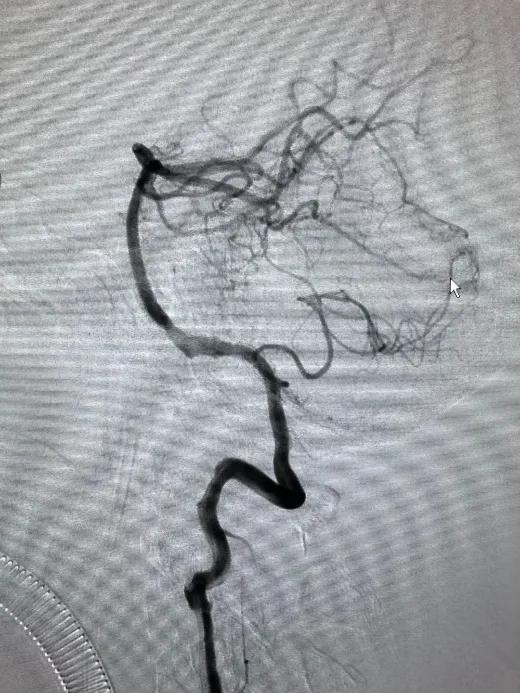

术后造影

造影见载瘤动脉通畅,支架打开、贴壁、覆盖满意,夹层动脉瘤未显影,脊髓前动脉显影良好,结束手术。